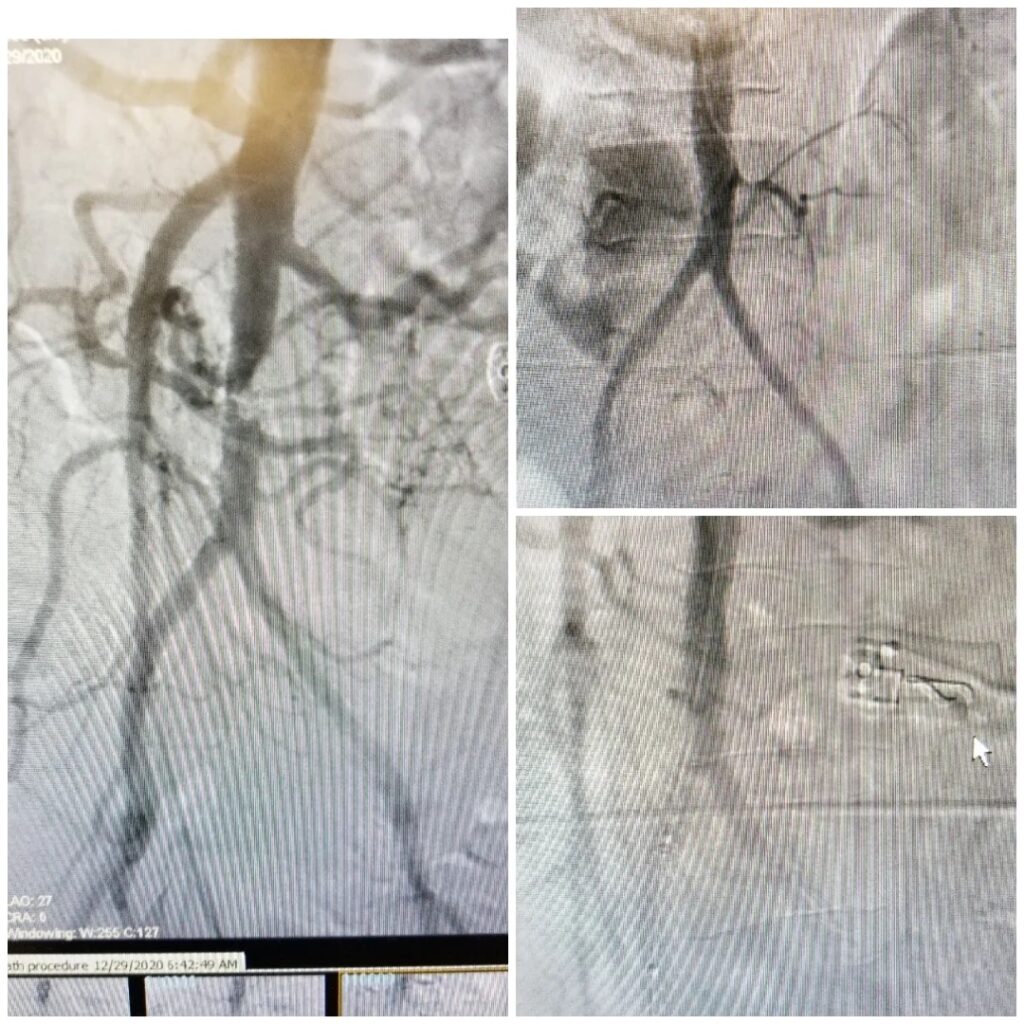

The technology was used to treat a critical stenosis in abdominal aorta, a condition which is typically treated with open surgery and several days of hospitalization. Dr. Agarwal used this new technology to place a stent to open the blockage, without the need for major surgery, and the patient was discharged the same day.